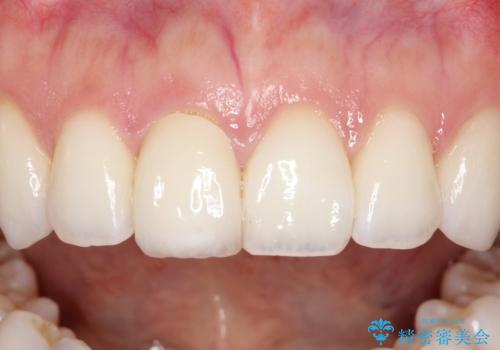

【オールセラミッククラウン】前歯の被せ物

- 矯正後、前歯被せ物のやりかえを希望され治療を行いました。

オールセラミック(スペシャル)にて修復しております。

オールセラミッククラウンは切縁の透明感や色調のグラデーションを再現することができます。